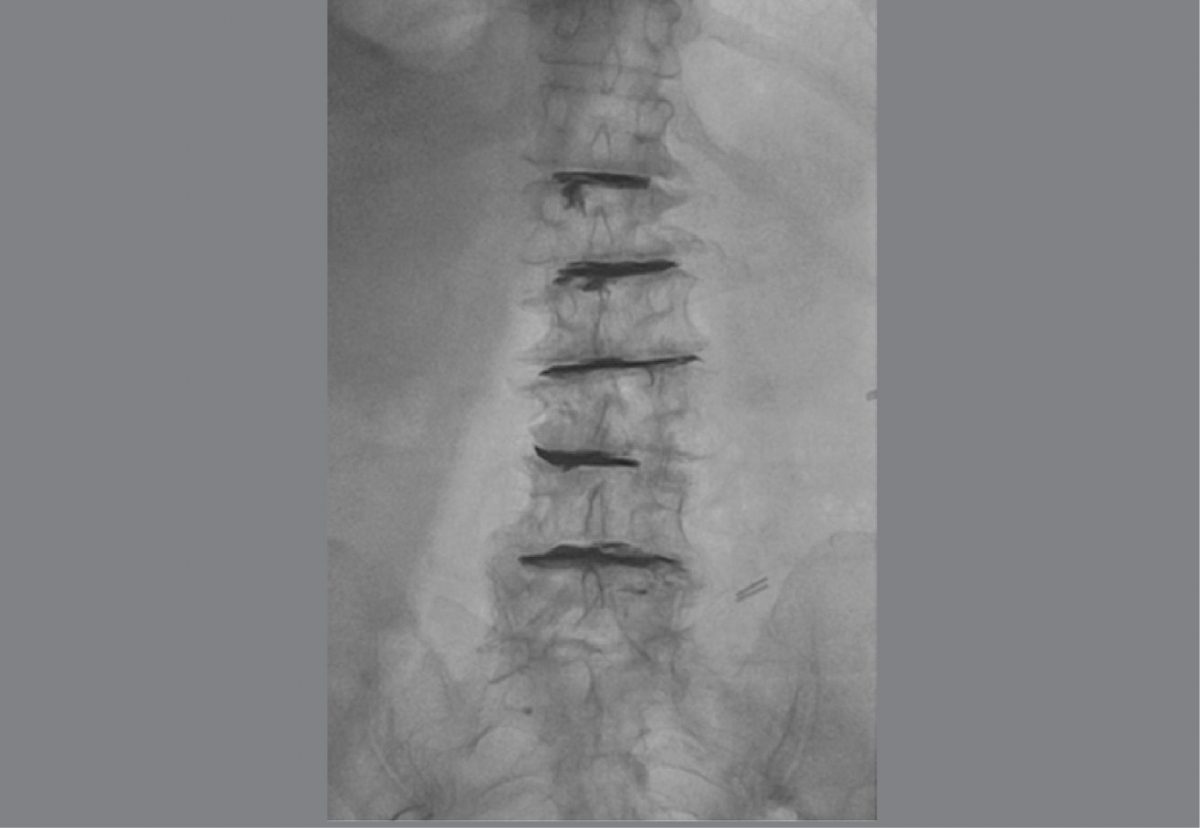

O cimento discoplastia percutânea (PCD) é uma técnica cirúrgica minimamente invasiva, que proporciona estabilização segmentar e efeito descompressivo indireto nos casos de doença discal degenerativa grave com fenômeno de vácuo, útil em pacientes com comorbidades que contra-indicam procedimentos cirúrgicos agressivos.

Percutaneous cement discoplasty (PCD) is a minimally invasive surgical technique, which provides segmental stabilization and an indirect decompression effect in cases of severe degenerative disc disease with vacuum phenomenon, useful in patients with comorbidities that contraindicate invasive surgical procedures.

6 cases of PCD were included, of which 5 had a diagnosis of dyscarthrosis and 1 dyscarthrosis with spondylolisthesis. 4 female and 2 male patients. In 3 patients, PCD was performed in 1 segment and in 3 patients in multiple segments. Regarding the clinical result, an improvement was presented in 5 of the patients (mean 5.6 VAS points), 1 of the patients did not present improvement and required another surgical intervention.

PCD is a minimally invasive technique useful in the treatment of spine pain secondary to degenerative disc disease in those patients with comorbidities that contraindicate a major procedure. Indirect foraminal decompression by PCD in one or more segments appears to contribute to pain relief.